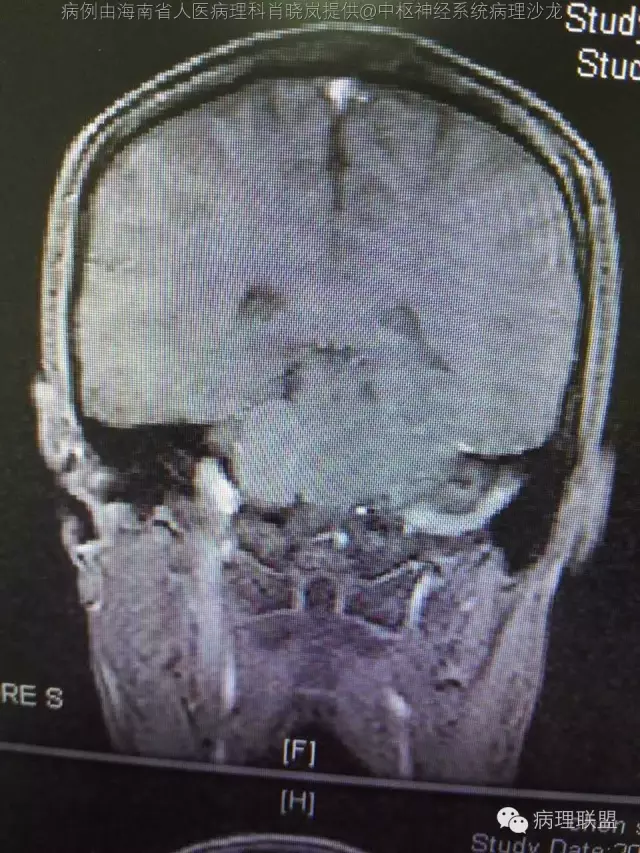

男,36岁。右面部麻木1月余。手术所见:右CPA区见5Ⅹ4cm肿块,灰褐色,血供丰富,质韧,界清。临床诊断:右侧桥小脑角区占位:脑膜瘤。大体检查:灰黑色碎组织一堆,大小2.5Ⅹ2.5x0.5cm,免疫S100,HMB45阳性。Ki67指数低。(病例由海南省人医病理科肖晓岚提供,致谢!)

@海南省人医病理科肖晓岚 影像也是符合黑色素相关肿瘤,可请影像专业的老师分析一下CT结合MR对产生黑色素的病变还是具有一定的特征性的,本例黑色素含量似乎不太多,所以跟脑膜瘤差不太多了,需要请影像老师分析!